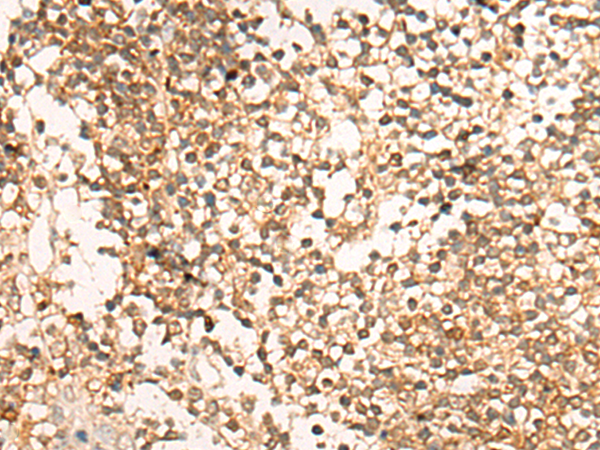

IHC positive control: |

Human colorectal cancer and Human tonsil |